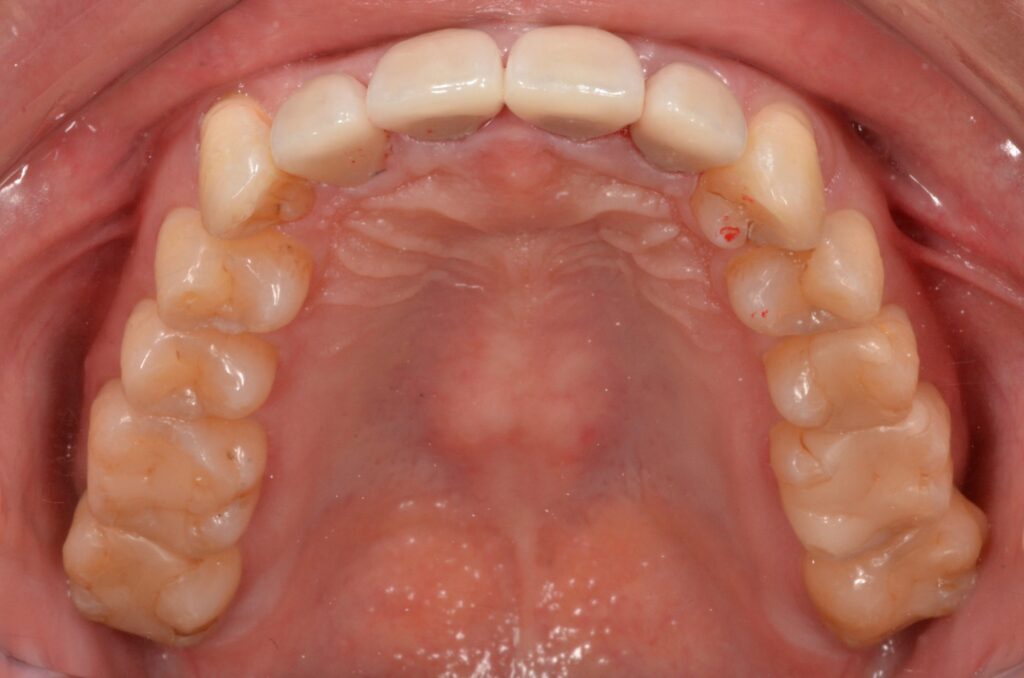

マウスピースでゆっくりと歯並びが治ったので、周りに気づかれずに済みました。治療後に以前の写真を見て驚きました。

| 治療方法 | マウスピース矯正治療(インビザラインシステム) セラミック治療 |

| 治療期間 | 2年 |

| 治療費 | マウスピース矯正治療 125万円 セラミック治療 20万円/1本 |